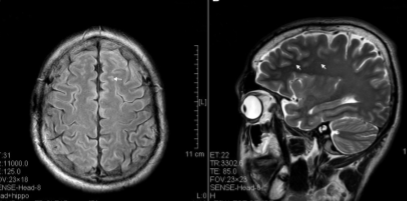

The brain is heavily affected by prolonged ketamine use, in most cases it destroys multiple regions of the brain. According to Chunmei Wang of the Brain Research Center, Institute of Chinese Medicine “the brain regions affected were prefrontal, parietal, occipital, limbic, brainstem and corpus striatum. The lesions affected both the gray and white matter” (5). (see fig. 2).

Fig. 2. The left shows a normal brain with no drug abuse. The right is an addicts’ brain who has done a half gram of ketamine each day for seven years. You can see that some sections of the brain almost looked smashed or caved in, this is where it has deteriorated from the usage of ketamine from Chunmei Wang et al.; “Brain damages in ketamine addicts as revealed by magnetic resonance imaging”; Frontiers in Neuroanatomy, vol. 7, no. 23, 2013; pp. 1-6